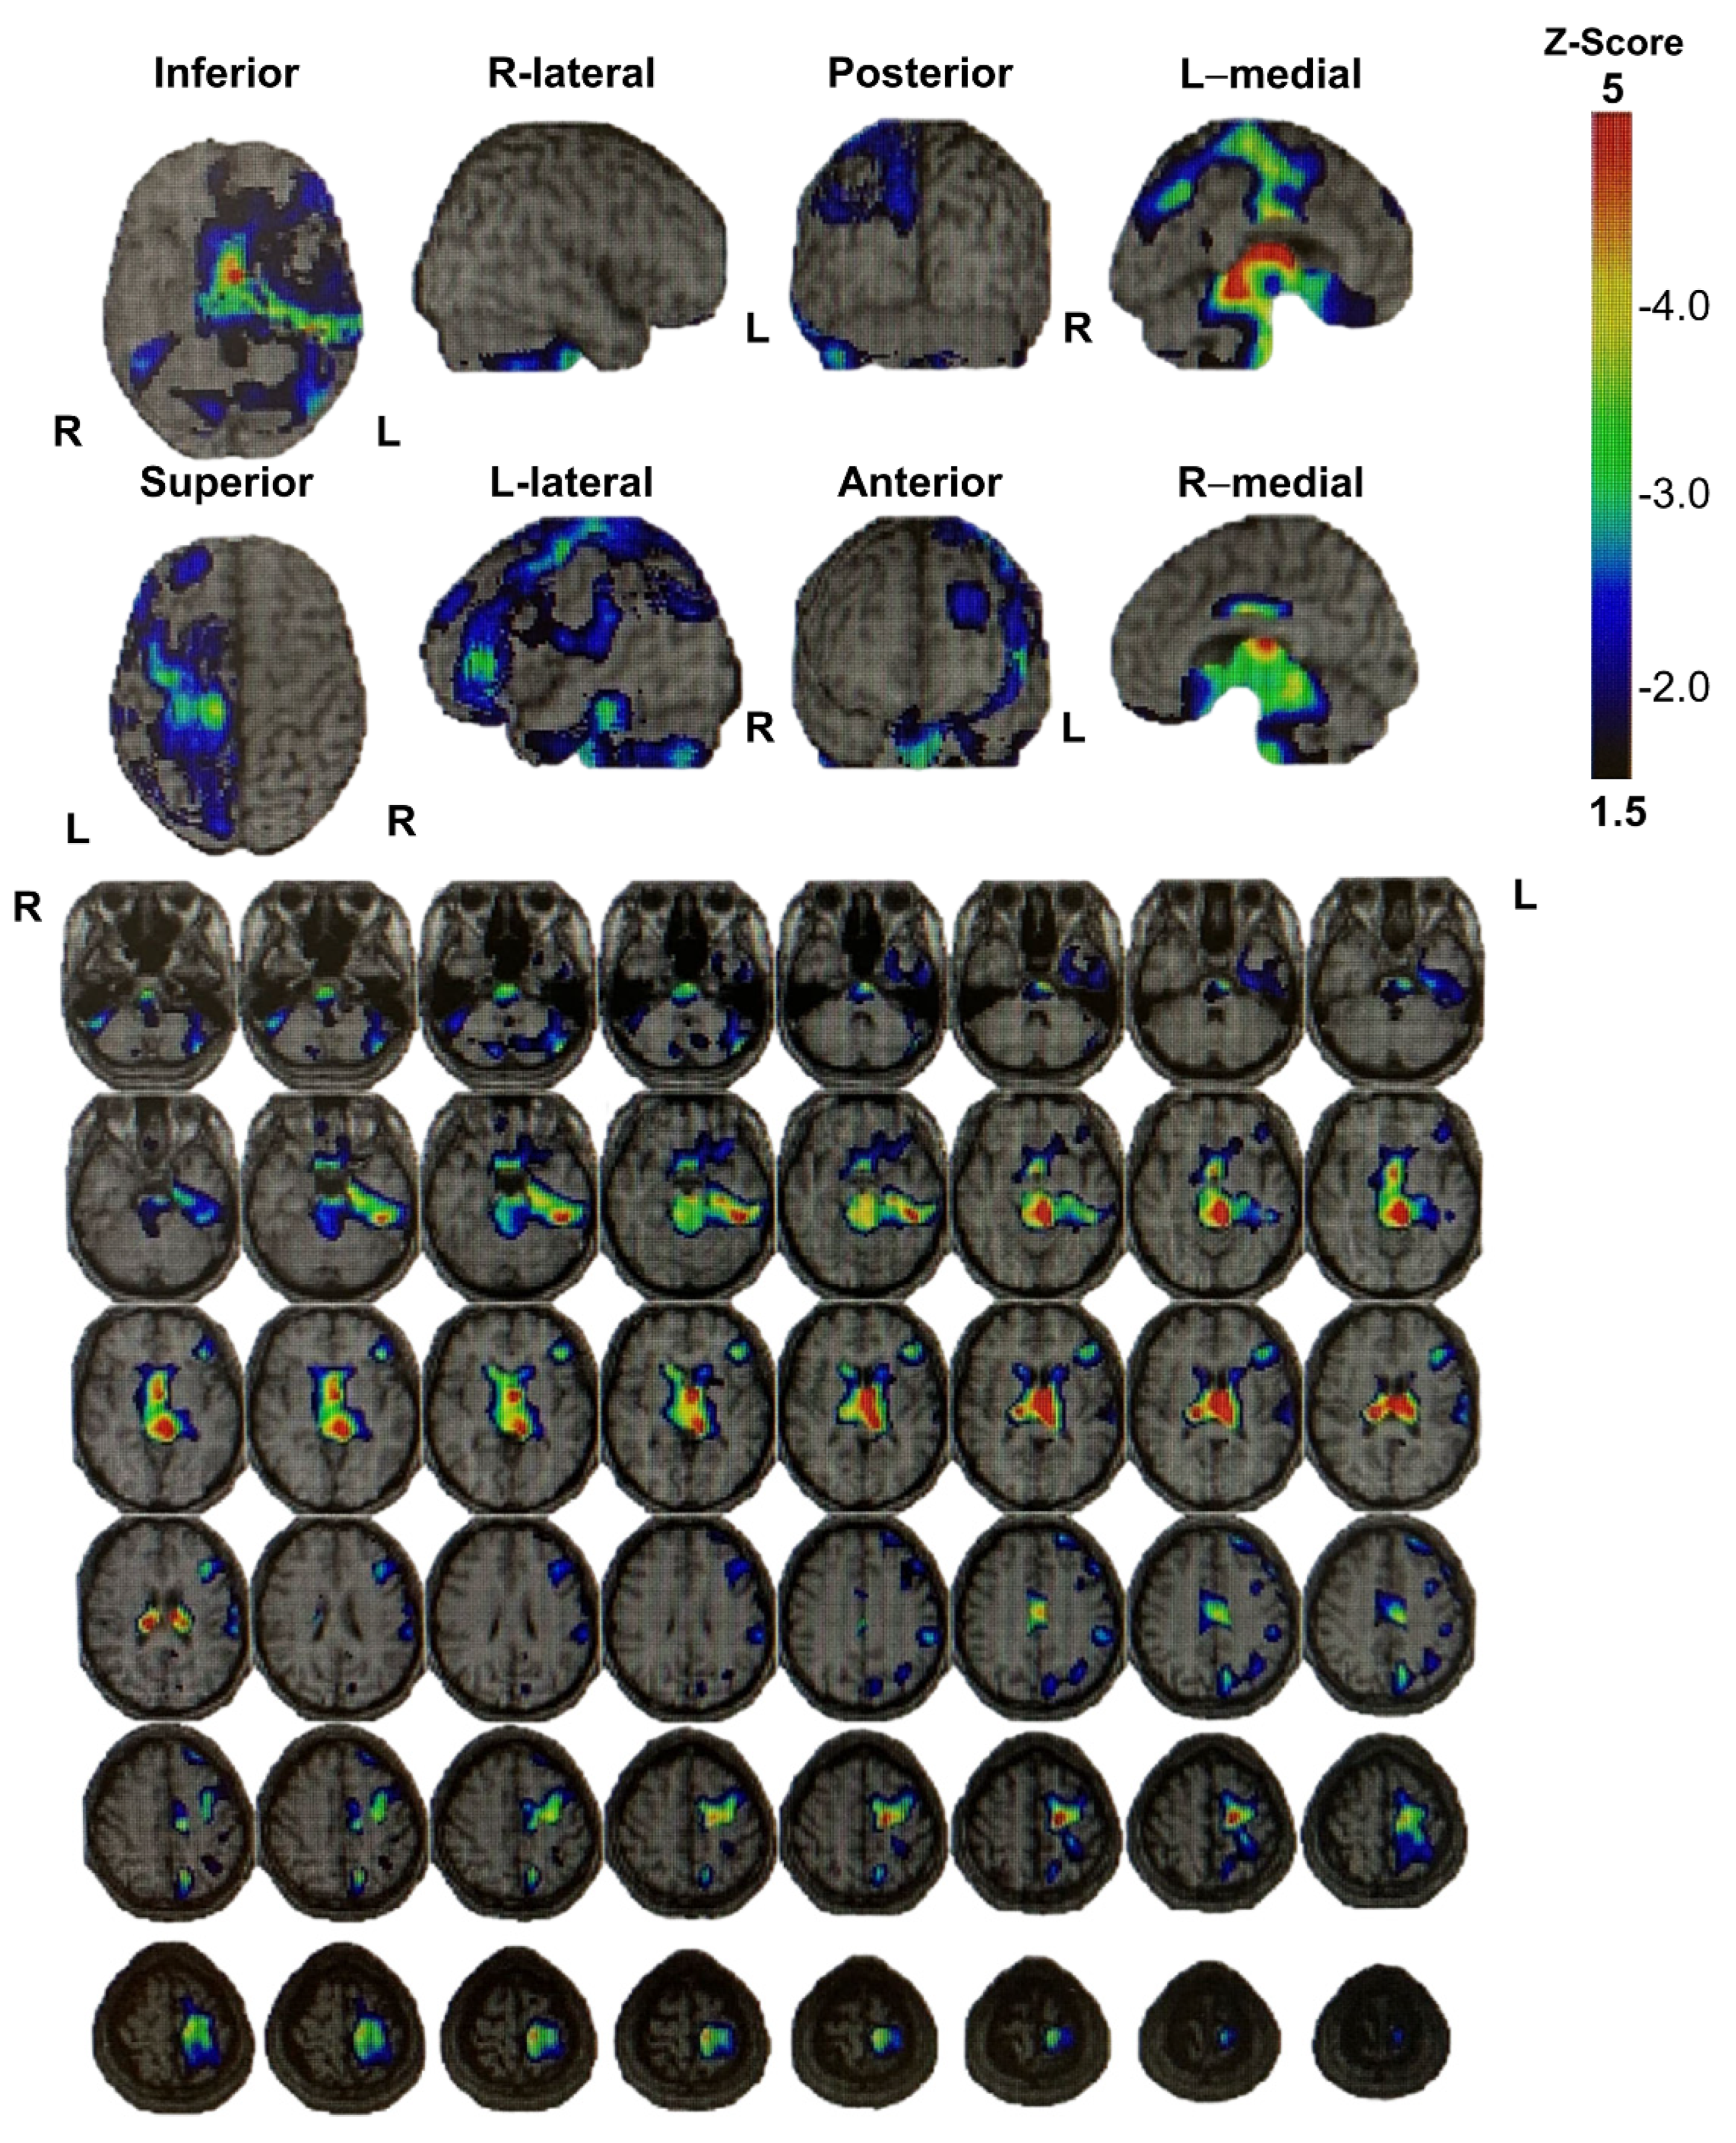

During the medical examination, the patient expressed sincere remorse over the alcohol-related problems and desired to seek solutions. Accordingly, we started a detailed examination for higher brain dysfunction and requested a psychiatric assessment for specialized treatment of alcohol dependence/abuse. The patient was diagnosed with higher brain dysfunction based on social behavioral deficits in daily life and memory deficits confirmed by neuropsychological testing. Figure 2 and Figure 3 show the results of brain imaging performed on his first visit to our department. MRI revealed cerebral atrophy in the region from the left frontal lobe to the parietal lobe; furthermore, SPECT (Single Photon Emission Computed Tomography) confirmed decreased blood flow in the region from the left frontal lobe to the parietal lobe, as well as bilaterally decreased blood flow in the basal ganglia (near the thalamus) and brain stem (near the midbrain). Table 2 shows the results and timeline of the neuropsychological tests performed. His intelligence was consistently at the lower limit of normal from the examination 1 year after the injury to the most recent examination 23 years after injury, and his memory impairment was consistently conspicuous at all examination time points. Other tests showed no apparent decline. He consumed alcohol while receiving treatment for alcoholism in an alcoholic rehabilitation facility, after stealing alcoholic drinks from a convenience store. Currently, his alcohol impulse control disorder persists with repeated episodes of alcohol consumption and difficult behavior after sneaking away from home. At the age of 38 years, he was caught shoplifting at a home improvement store while sober and is currently on trial for impulsive behavior regardless of alcohol consumption. He has been arrested many times, with his mother expressing her frustration saying, “It would have been better if he died in the car accident if he was going to cause so much trouble to others”.

Figure 3. I-123-iodoamphetamine single-photon emission computed tomography images of Patient 2 show decreased blood flow in the region from the left frontal lobe to the parietal lobe, as well as bilaterally decreased blood flow in the basal ganglia (near the thalamus) and brain stem (near the midbrain).

The onset of disinhibition could be attributed to injury of the basal ganglia, which was observed on MRI/SPECT in both cases. Components of the basal ganglia include the corpus striatum (the putamen, caudate nucleus, and nucleus accumbens (located at the inferior end of the corpus striatum)), globus pallidus/subthalamic nucleus/substantia nigra, red nucleus, and lateral vestibular nucleus [11]. Both cases may have suffered damage to the nucleus accumbens, which is the pleasure center. Damage to the nucleus accumbens, orbitofrontal cortex (OFC), or inferior prefrontal cortex circuit (behavioral inhibition system), as part of the frontal basal ganglia thalamic circuit [12], may have resulted in the observed sexual disinhibition and alcohol abuse (dependence/addiction). There has been a growing interest in the indirect and hyper-direct pathways of the cerebral cortex–basal ganglia circuit as crucial neurological basis for behavioral inhibition in humans [13,14,15,16], which could have resulted in poor behavioral control in both cases. Alternatively, impulse control disorders could be linked to the nigrostriatal dopaminergic system. Under normal conditions of impulse control by the nigrostriatal dopamine system, the activity of dopamine neurons in the compact part of the substantia nigra increases in response to inappropriate behavior. This leads to an increase in neuronal activity in the caudate nucleus, a striate area that receives projections from the aforementioned dopamine neurons, which inhibits inappropriate behavior. Conversely, dysfunction of the dopamine system in the pars compacta of the substantia nigra or caudate nucleus results in an inability to suppress inappropriate behavior through these pathways [17]. In Case 1, MRI revealed DAI in the midbrain and right caudate nucleus; moreover, SPECT in Case 2 showed decreased blood flow around the midbrain. Therefore, the inability to suppress inappropriate actions could be attributed to a failure of the aforementioned system.